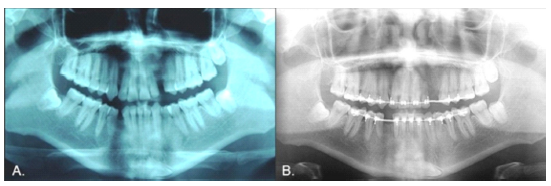

Case 2

Female, 15 years old. As with Case 1, the inferior left canine was the only primary tooth remaining in the mouth (Fig. 3). The radiograph showed that the 3.3 exhibited a type 2 transmigration (Figs. 4, A and B). The tooth was located closer to the mandible edge than in Case 1, precluding the use of orthodontic traction, and it was decided to monitor the tooth. Dental protrusion was the initial reason for the appointment, and the patient requested orthodontic treatment of this condition. Because the 3.3 was far from the roots of the neighboring teeth, the orthodontist decided there would be no risk in moving teeth in this zone. To correct the protrusion, the first premolars were extracted (except for quadrant 3 since the 3.3 was transmigrated). The 3.3 would not be restored in this treatment since the 3.4 would take its place. The 1-year follow-up panoramic x-ray showed no significant changes (Fig. 4C).